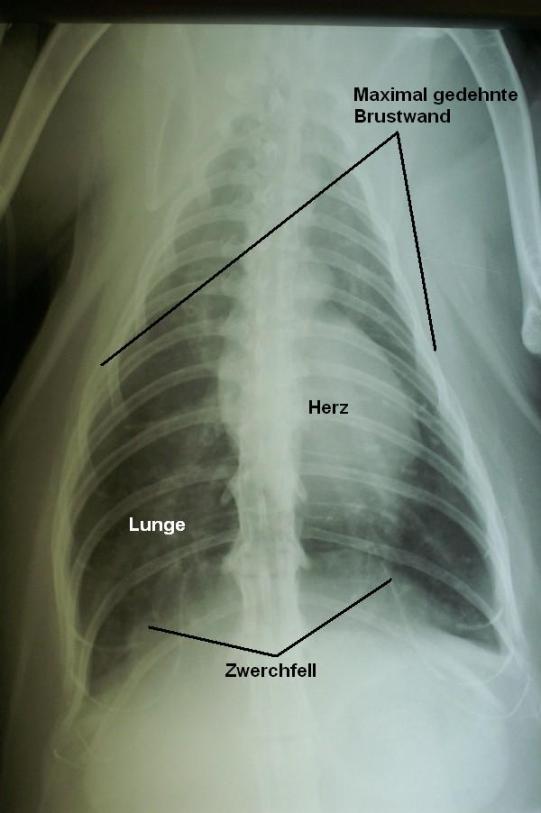

Währenddem der Katze immer noch Sauerstoff zugeführt wird, wird eine Röntgenaufnahme der Brust angefertigt, für die das Tier in der natürlichen, stressfreien Brustlage positioniert wird. Im Laufe der Nacht und bei verbesserter Atmung wird auch noch eine seitliche Brustaufnahme angefertigt.

Das Herz hat eine normale Grösse und Form. Die Lunge ist maximal gedehnt (Hyperinflation), was am praktisch flachen Zwerchfell (welches normalerweise kuppelartig gewölbt ist) und der maximal gedehnten Brustwand zu erkennen ist. Die Lunge ist diffus und generalisiert mit einem sogenannten „bronchointerstitiellen Muster“ verschattet.

Diese Befunde sind typisch für das feline Asthma (Katzenasthma).